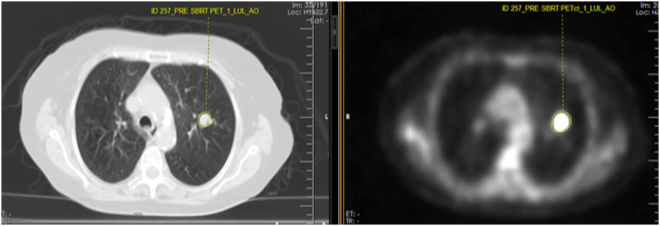

Figure 6.

Screenshot of the texture analysis software applied on a staging PET/CT study for a NSCLC patient before SBRT therapy. On the left is the CT image and on the right, is the PET image of the PET/CT at the exact same level. The manual contouring of the right lower lobe tumor on both images is noted. There was an event of distant metastasis and death. SUVmax = 1.9. The significantly low SUVmax failed to predict the poor clinical outcome as evidenced by the development of distant metastasis and ultimately death.

Figure 7.

Screenshot of the texture analysis software applied on a staging PET/CT study for a NSCLC patient before SBRT therapy. On the left is the CT image and on the right, is the PET image of the PET/CT at the exact same level. The manual contouring of the tumor on both images is noted. There was no clinical event. SUVmax = 11.4. In comparison to the patient in the Fig. 1, the higher SUVmax did not correlate with the absence of clinical event.